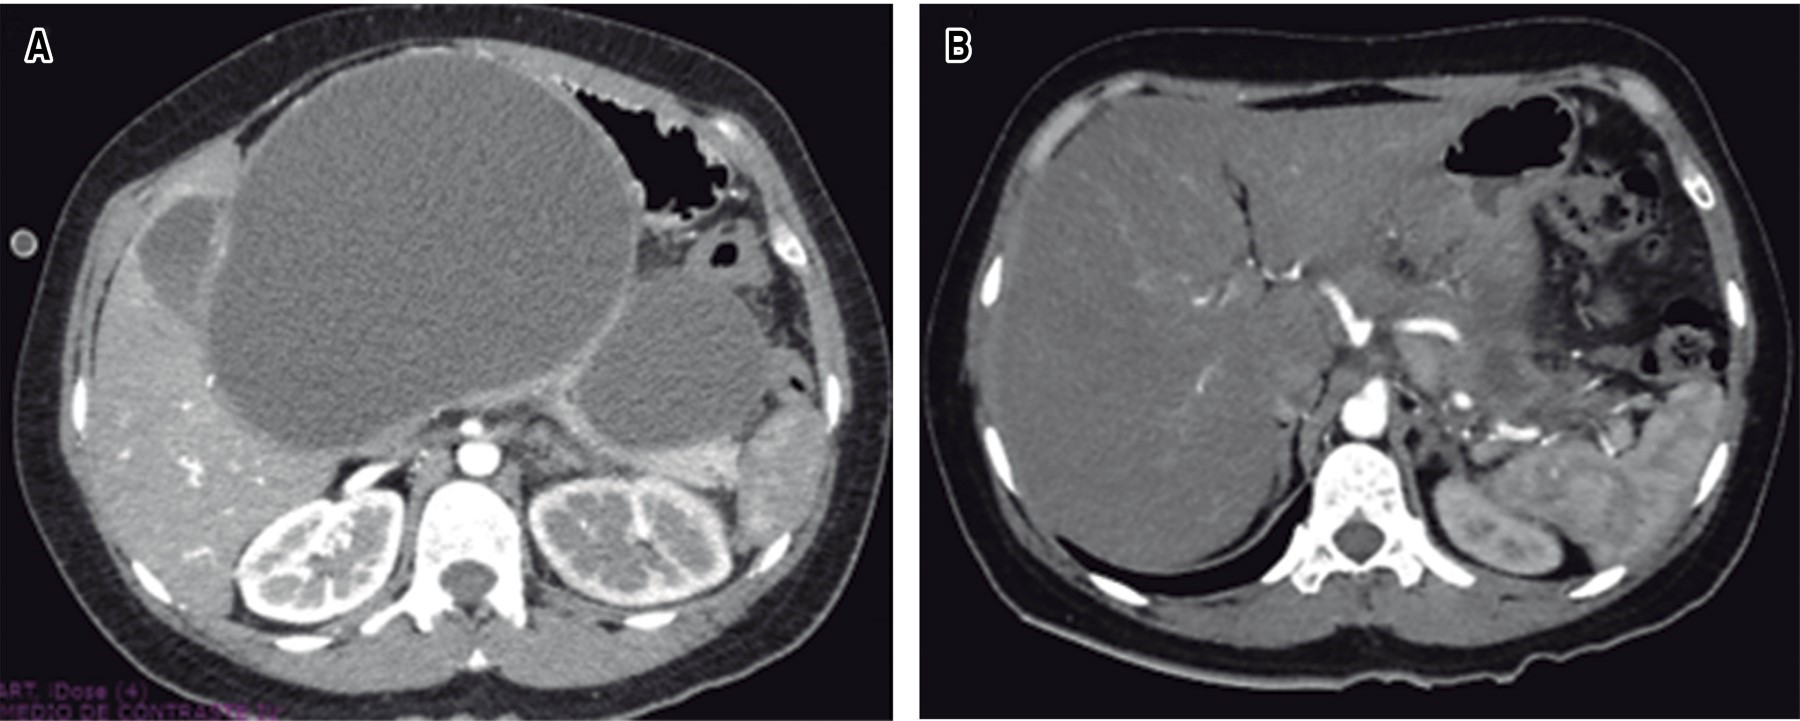

An abdominal CT scan with intravenous contrast was performed with a report of an enlarged pancreas with ovoid lesions on the head and body, measuring 229 × 137 × 182 mm with an approximate volume of 2,899 cm3 and a second lesion measuring 100 × 57 × 82 mm with an approximate volume of 238 cm3, with homogeneous density, thin walls, compatible with cystic lesions. The gallbladder measured 80 × 43 × 35 mm and had a thin wall with heterogeneous content due to a liquid-liquid level of biliary sediment (Figure 2).

Figure 2